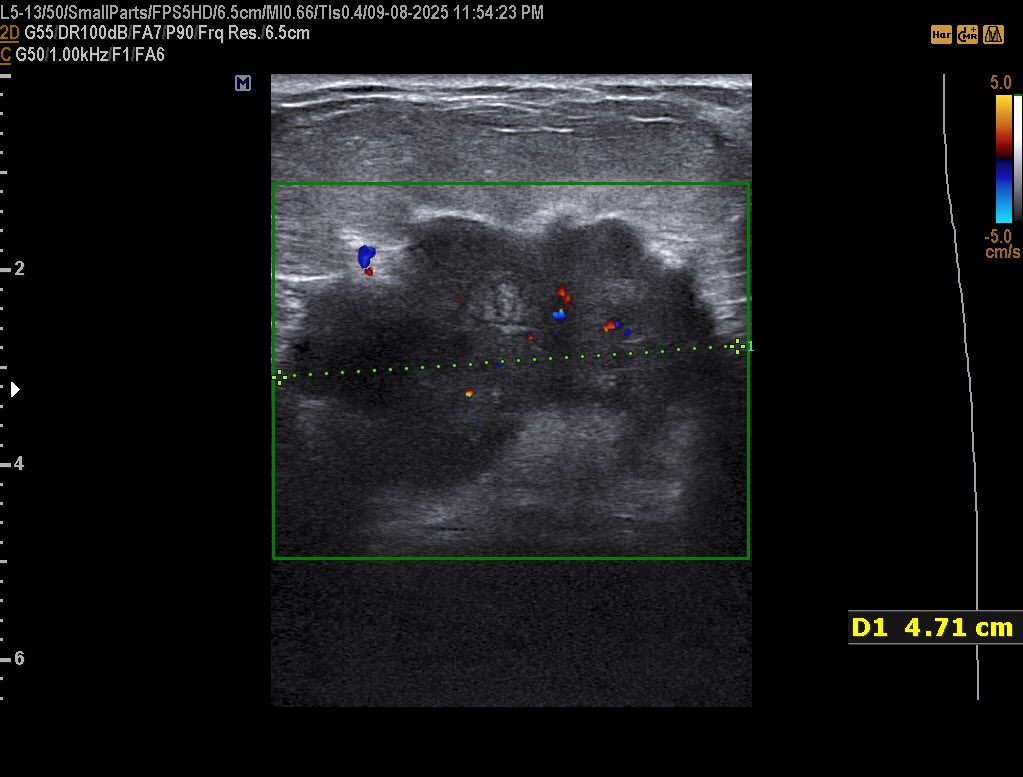

42 years female presented with a palpable painless hard and fixed Breast mass since 1 year BI-rads? #EchoTech @ABCDEcografia @dmiguelmolina @Omkolsoumyahoo1

42 years female presented with a palpable painless hard and fixed Breast mass since 1 year BI-rads? #EchoTech @ABCDEcografia @dmiguelmolina @Omkolsoumyahoo1